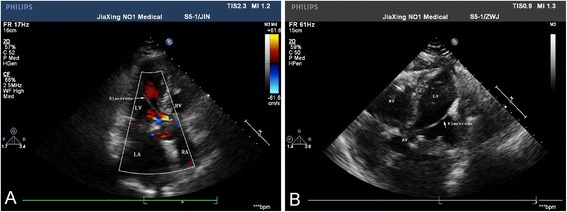

Both pacemaker function and Holter indicated favorable behavior of the pacemaker after the operation, and stitches were taken out one week later. Nine days later, the reexamination of cardiac ultrasound demonstrated as follows: postoperative state of mitral valve replacement, normal artificial biological mitral valve, enlargement of left atria, mild reflux of aortic valve, mitral valve flow spectrum showing a single peak, and pacemaker in ascending aorta and left ventricle (Fig. 1a, b). Chest computed tomography (CT) scan indicated that the pacemaker electrode was put into aorta and left ventricular (Fig. 2b, c), which suggested that the pacemaker had been put into subclavian artery by mistake and the pacing electrode was implanted in the left heart.

Fig. 1.

Cardiac ultrasound after operation. A Cardiac ultrasound demonstrated pacing electrode in ascending aorta and left ventricle. B Cardiac ultrasound demonstrated pacing electrode in ascending aorta and left ventricle